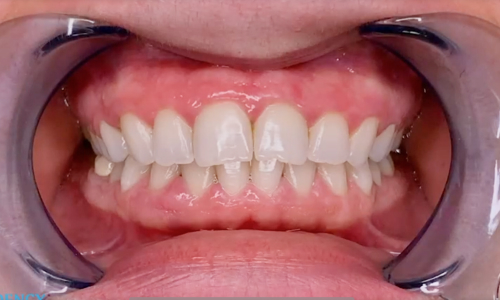

Пациент 25 лет обратился в стоматологическую клинику с жалобами на желтовато-коричневый оттенок зубов на верхней и нижней челюстях. Пациент курит.

Процедура прошла успешно за один приём, без боли или дискомфорта. После отбеливания зубы пациента осветлились на несколько оттенков.

Primo-1.jpg